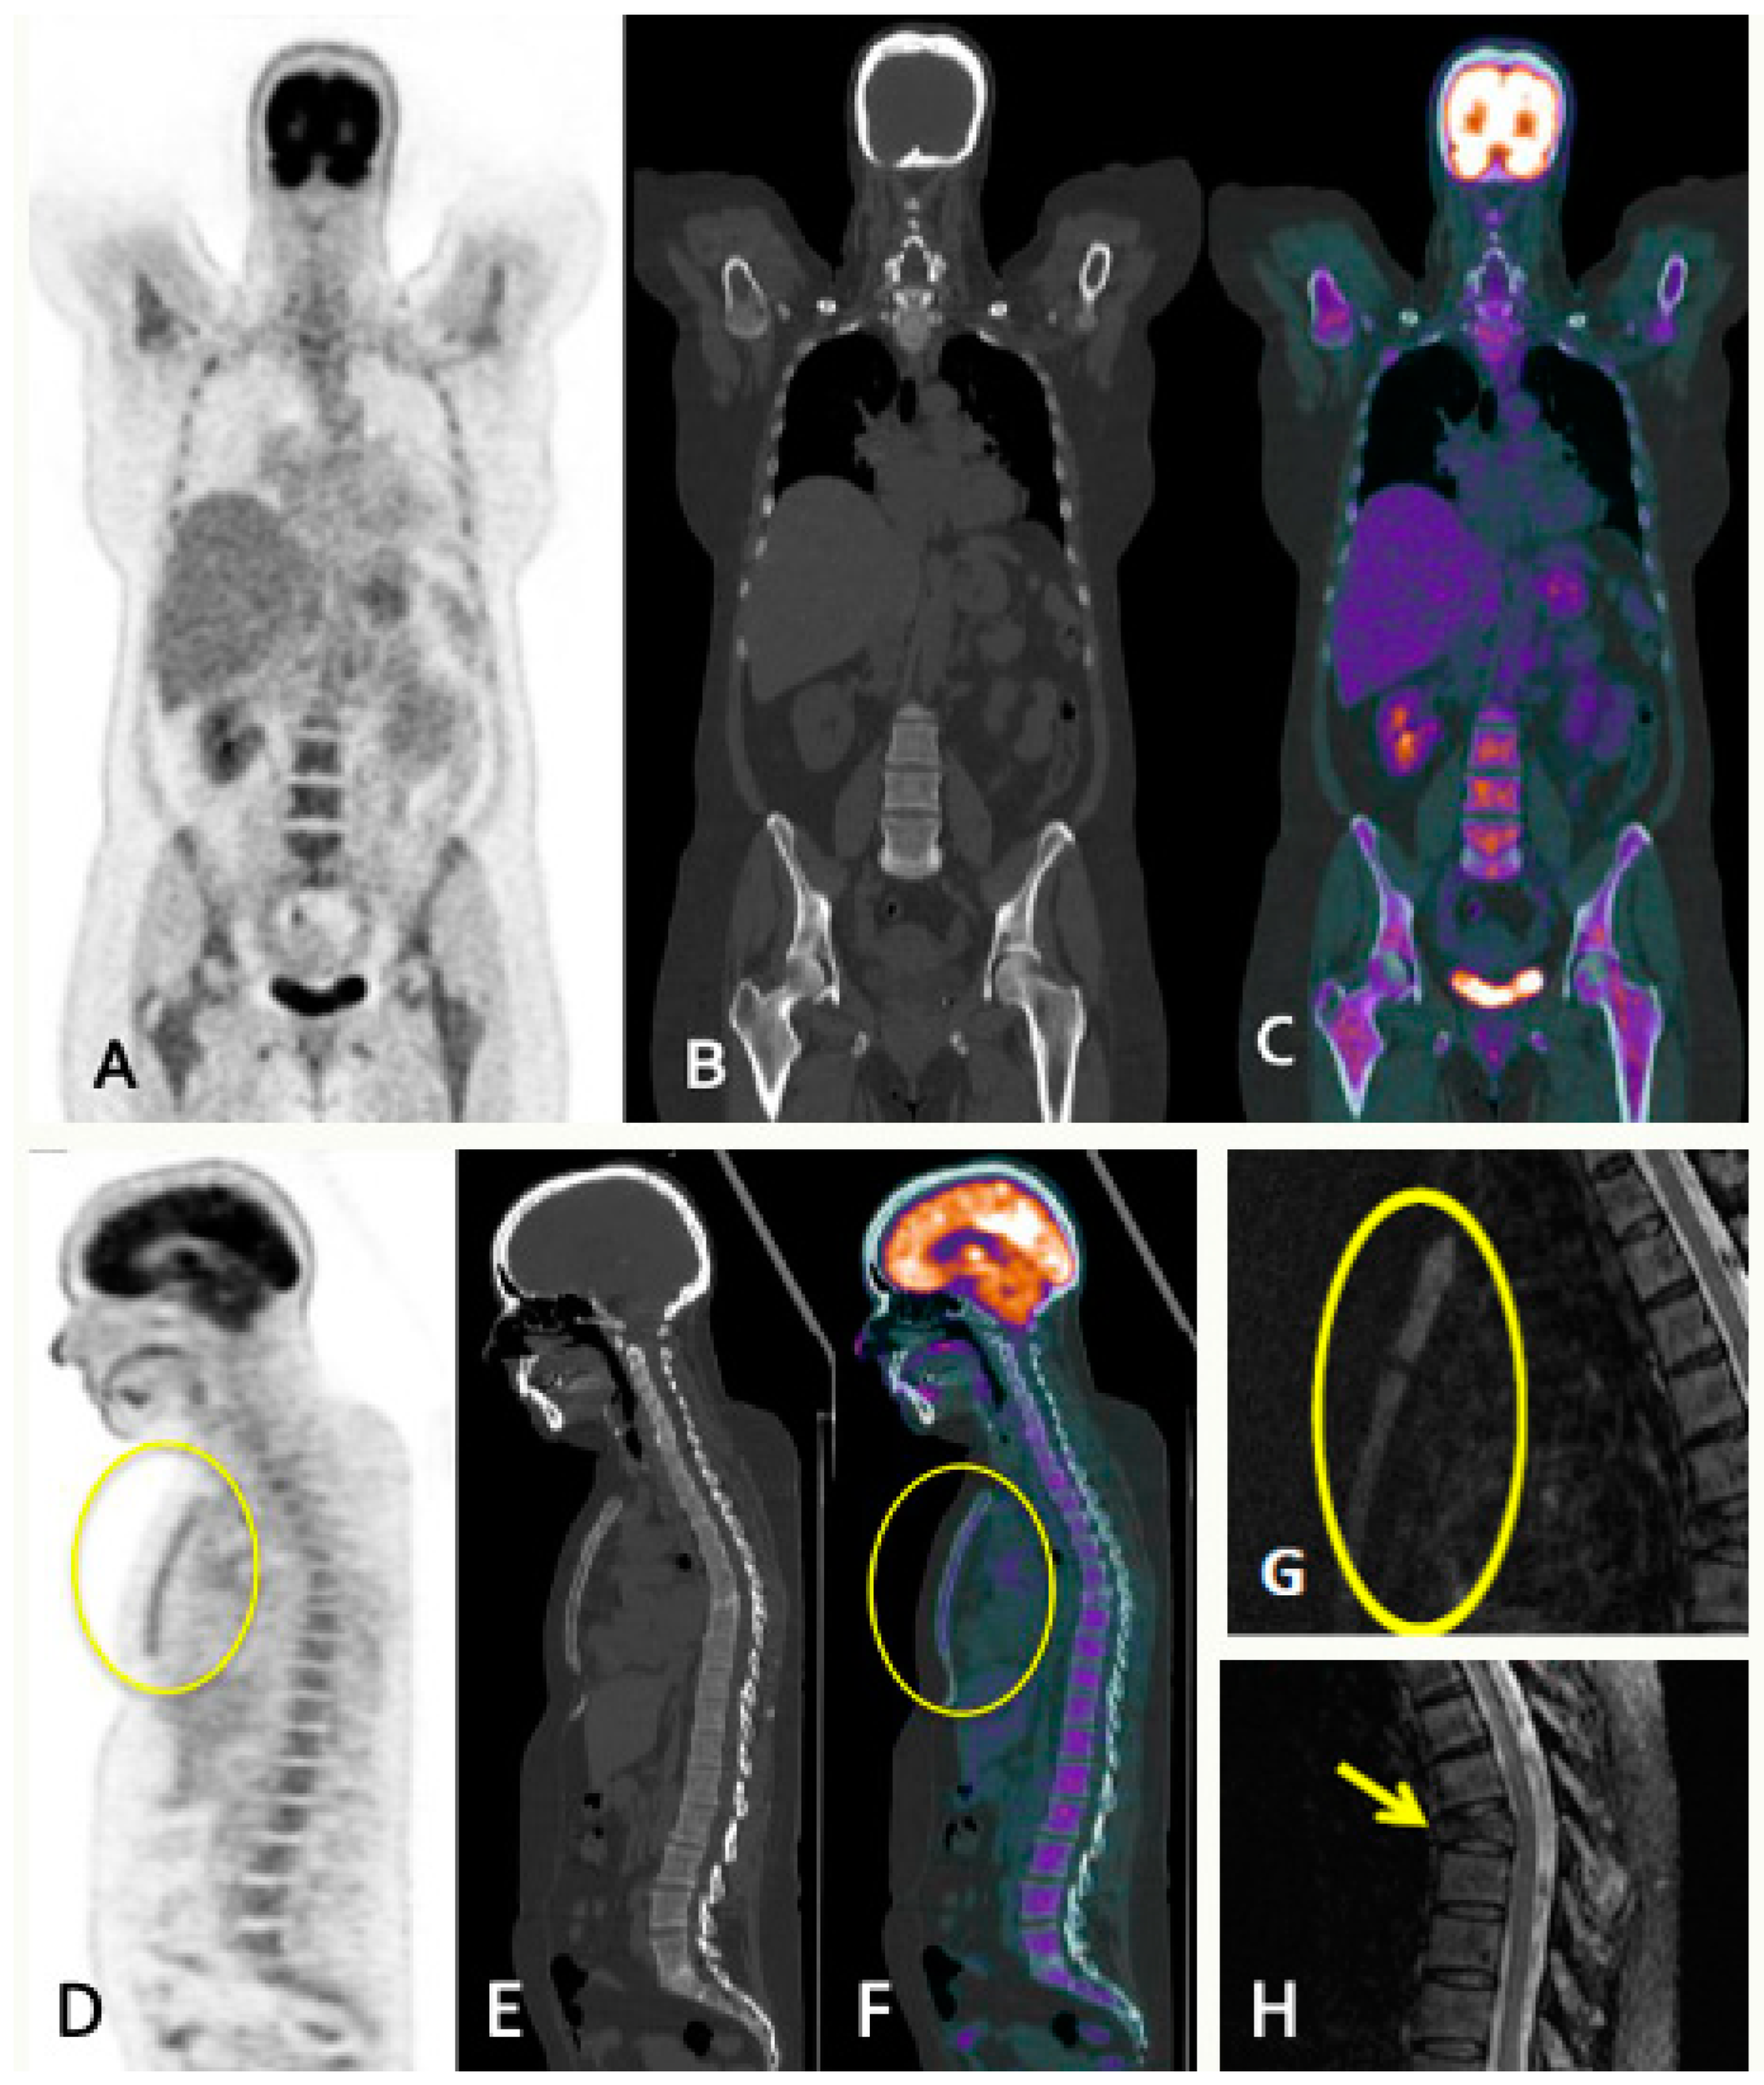

- Diffuse pattern: Diffuse disease can be suspected from a diffuse decreased signal on T1WI (either iso- or hypointense to intervertebral discs and muscle) and a diffuse increased signal throughout the marrow on T2FSWI, STIR, or high b-value DWI. Marrow ADC values above 600–700 μm2/s in a nontreated and newly diagnosed patient with MM could be used to increase confidence for the diagnosis of diffuse marrow involvement [33] (Figure 7). Due to potential false-positive findings, diffuse disease in imaging must be supported by bone marrow trephine biopsy [26].